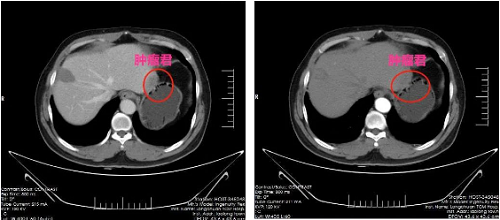

肝癌是我国发病率第三、致死率第四的恶性肿瘤。肝癌分原发性与继发性两类,其发病隐匿,初期可无明显症状或仅仅上腹部稍许胀闷不适,至晚期才有消瘦、黄疸、腹部包块等症状,因此成为严重危险我国人民群众身体健康的恶性肿瘤。近日,龙川县中医院外一科收治了一名肝癌患者,50岁男性,因腹腔镜乙状结肠中分化腺癌根治术后两年返院复查,复查结果提示肠道虽未见肿瘤复发,但肝脏S2段出现转移癌,CT提示未见他处转移,各项抽血检查以及胃镜、结肠镜未见明显异常。

患者因既往有外伤性脾破裂脾切除以及结肠癌根治手术史,腹腔的粘连较重。龙川县中医院外一科手术团队仔细分离腹腔粘连后,明确肝脏癌肿的部位,在距离癌肿旁1cm连部分正常肝组织一并切除,达到R0切除,术后病理提示切缘断端已无癌组织残留,亦即根治性切除。